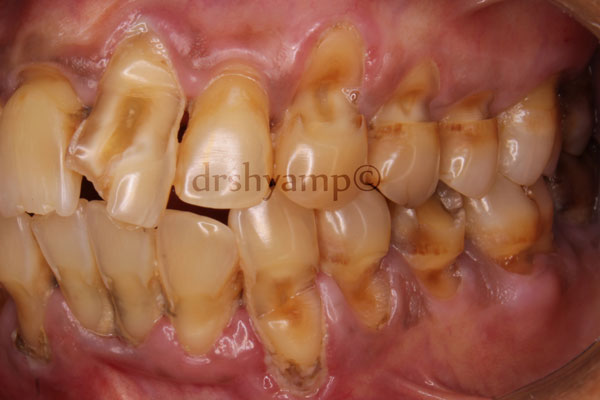

Abrasion refers to the loss of tooth substance induced by mechanical wear other than that of mastication. Abrasion results in saucer-shaped or wedge-shaped indentations with a smooth, shiny surface. Improper toothbrushing with an abrasive dentifrice and the action of clasps are common causes of abrasio.n

Horizontal brushing at right angles to the vertical axis of the teeth results in the severest loss of tooth substance. Occasionally, abrasion of the incisal edges results from habits such as holding objects (e.g., bobby pin, tacks) between the teeth.

Attrition is occlusal wear resulting from functional contacts with opposing teeth. A certain amount of tooth wear is physiologic, but accelerated wear may occur when abnormal anatomic or unusual functional factors are present. Significant amount of attrition in young adults is unlikely to occur from functional wear and is probably the result of bruxing / clenching / tooth grinding activity.

erosion is a sharply defined, wedge-shaped depression in the cervical area of the facial tooth surface. Erosion generally affects a group of teeth. Suggested causes include decalcification by acidic beverages or citrus fruits and the combined effect of acid salivary secretion and friction